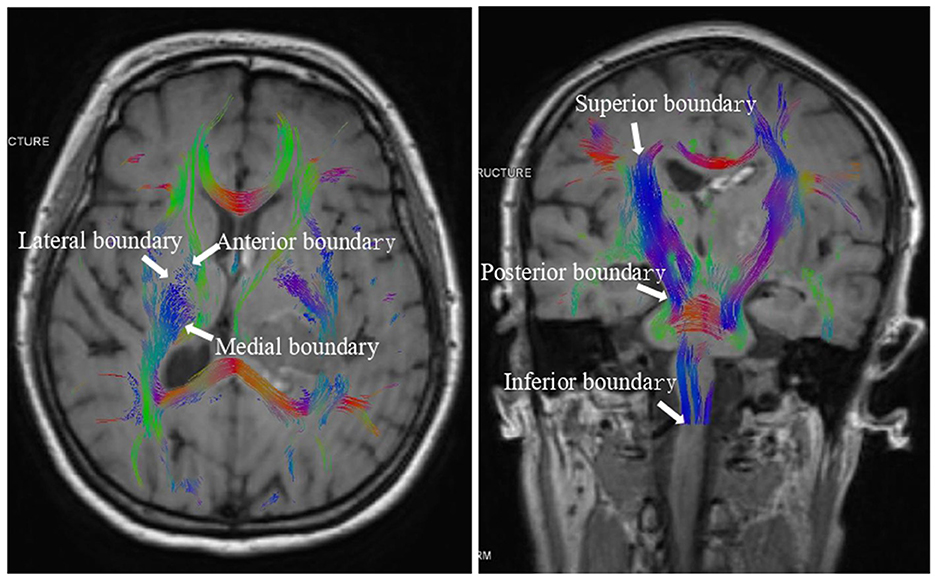

On the CST 3D image, manually delineate the region of interest (ROI) of the posterior CST of the internal capsule, with the anterior boundary defined by the anterior limb of the internal capsule and the posterior boundary by end of the caudate nucleus, the posterior boundary by the midbrain, the medial boundary by the medial wall of the lateral ventricle, the lateral boundary by the putamen, the superior boundary by the cerebral cortex, and the inferior boundary by the medulla (Figure 1). Then, measure these regions' FA, MD, RD, and AD values. The DICOM data were imported into the Remebot software system to reconstruct the FA maps, directional coded color maps, and bilateral 3D CST maps to evaluate the extent of CST damage and recovery. FA, MD, RD, and AD values for the same patient were assessed three times by two senior neuroimaging physicians at Baise People's Hospital and the Affiliated Hospital of Youjiang Medical College of Nationalities. The mean of all measurements was utilized as the definitive value for this patient to ensure the reproducibility and generalizability of the results.

Figure 1

The boundary of the region of interest (ROI) of the posterior CST of the internal capsule.